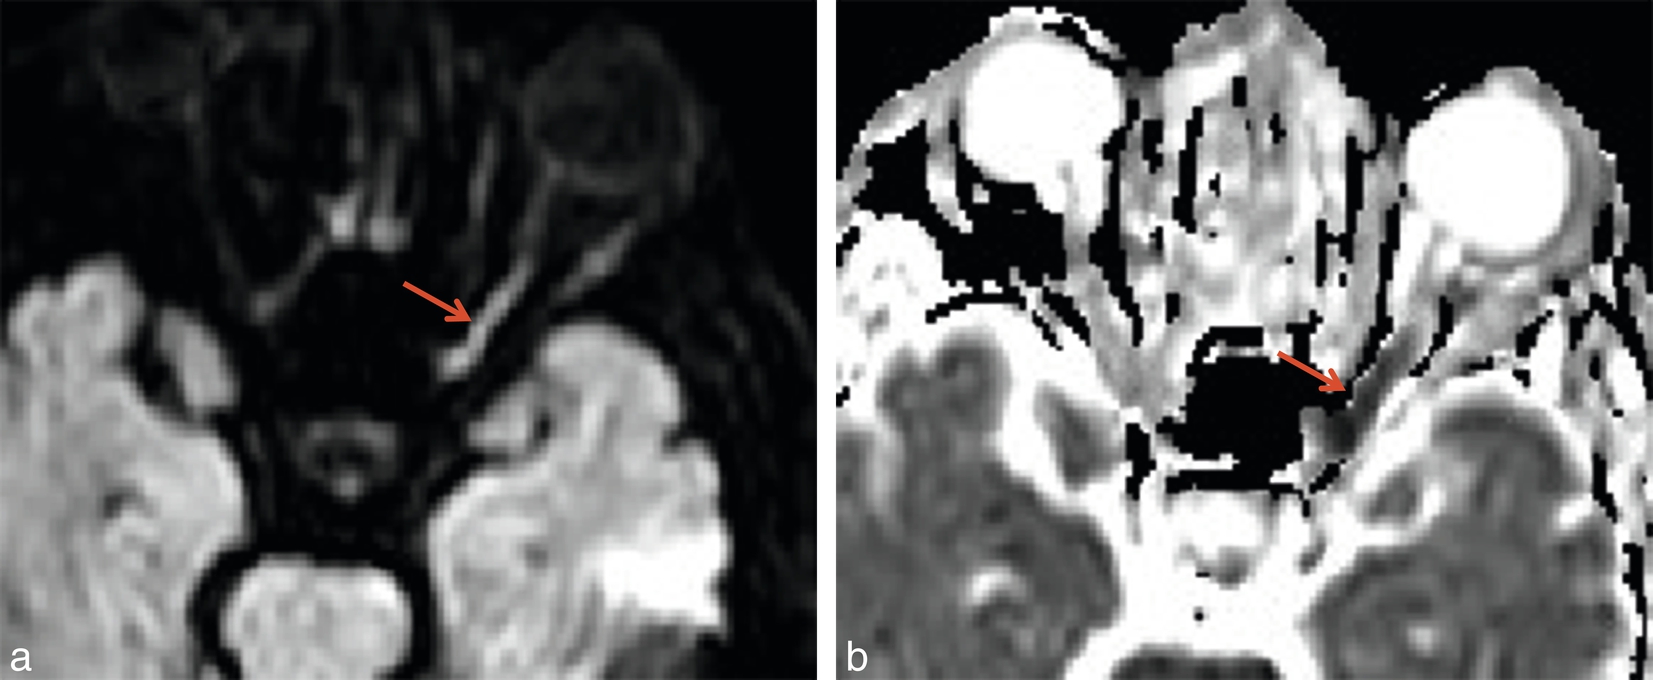

Dans un contexte non traumatique, cette baisse visuelle brutale traduit a priori une atteinte vasculaire. S'il existe un déficit altitudinal associé à un œdème papillaire, elle évoque une NOIA aiguë et peut justifier la réalisation d'une IRM encéphalique avec un protocole de type vasculaire en cas de suspicion d'artérite à cellules géantes, de trouble visuel transitoire précédant la baisse visuelle ou de doute diagnostique. Cet examen pourra exceptionnellement mettre en évidence l'ischémie de la papille en diffusion (fig. 2-48

Fig. 2-48

Ischémie de la tête du nerf optique (flèches rouges) en diffusion(a) et ADC(b).

).

Un cas particulier est représenté par les neuropathies optiques ischémiques postérieures, compliquant en particulier la chirurgie du rachis (fig. 2-49

Fig. 2-49

Ischémie postopératoire (hernie discale) du nerf optique gauche (flèches rouges) en hypersignal diffusion(a), avec ADC bas(b).

). Le bilan d'imagerie éventuel est centré sur le nerf optique pour éliminer une autre cause.